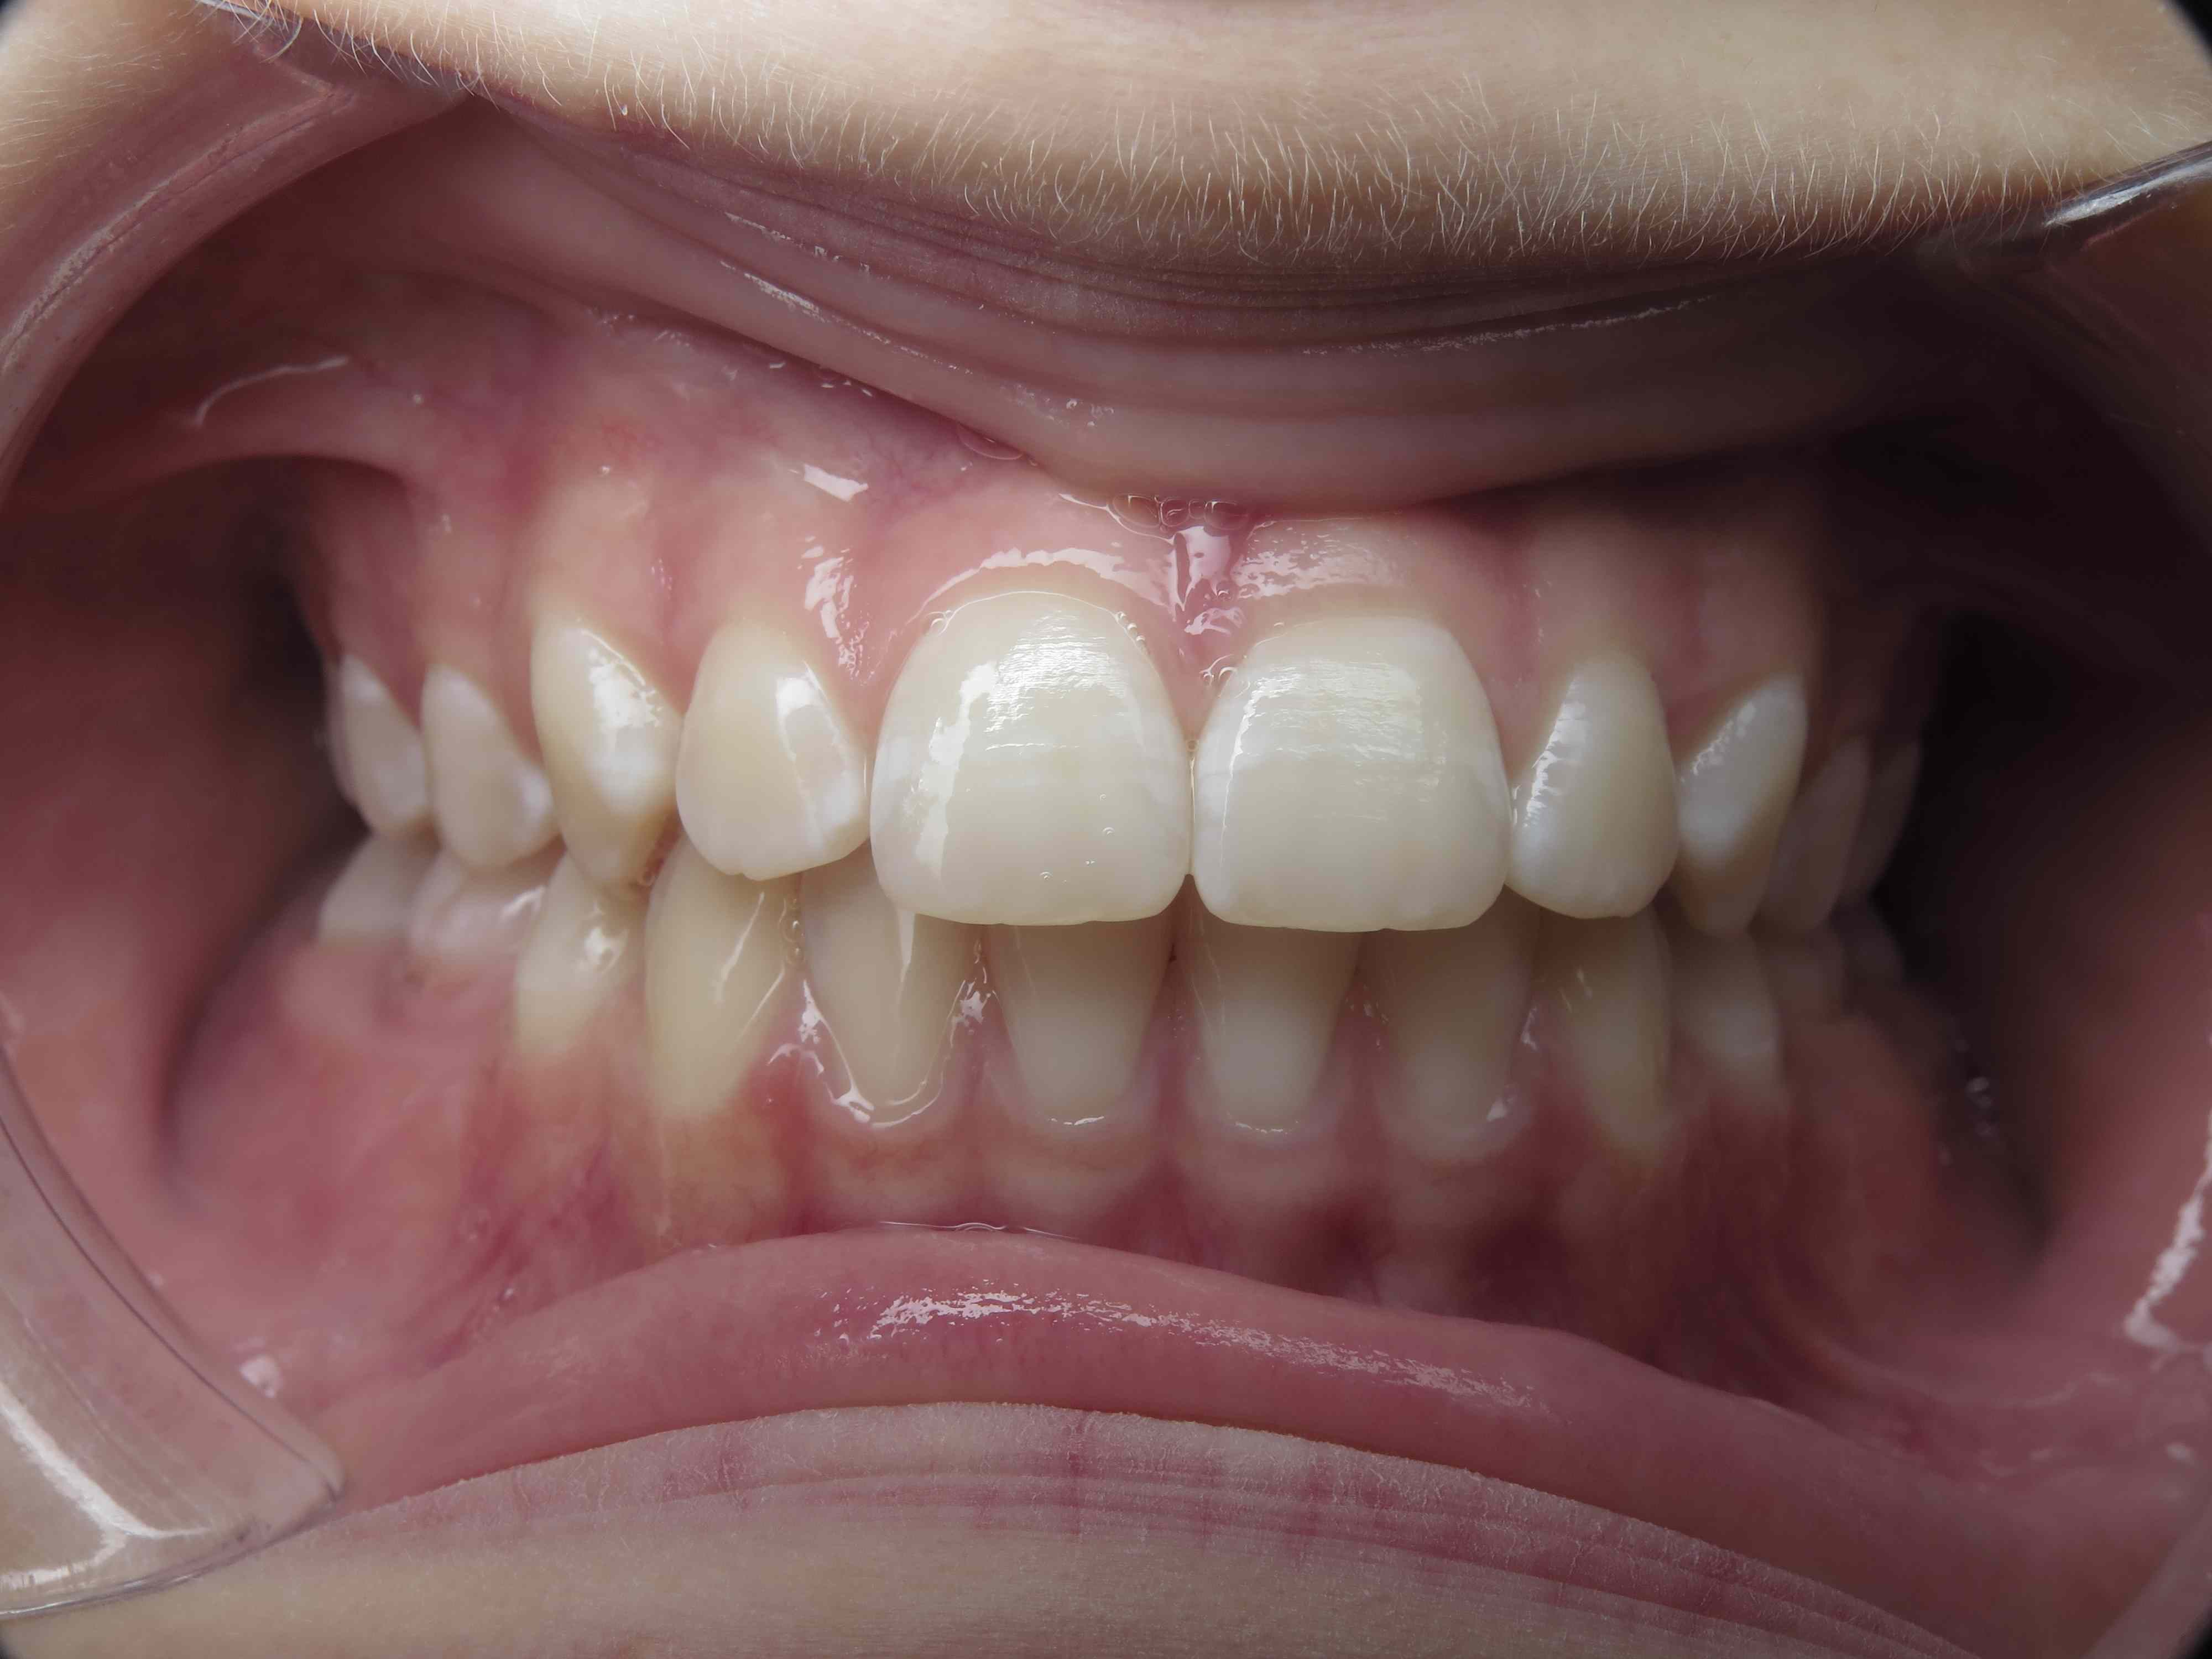

12 béance inversé droit 4 ans

inversion postérieur coté droit et espace entre les dents du haut et du bas (diastèmes)

bilan début et en cours de traitement